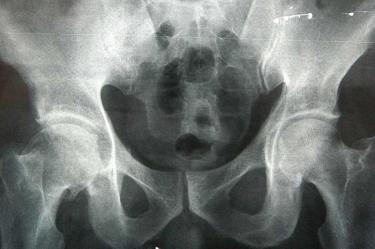

Añadió que aunque puede presentarse en cualquier hueso, la fractura de cadera es la más peligrosa, por ser altamente discapacitante e incluso puede llevar a la muerte, ya que cuatro de cada 10 personas que la sufren, no rebasan el siguiente año de vida a causa de diversas complicaciones como infecciones pulmonares, trombosis y formación de ulceras, por la poca o nula movilidad de quienes quedan postrados en una cama o limitados a una silla de ruedas.

El doctor Torres Martínez señaló que al año se presentan alrededor de 21 mil casos de fractura de cadera y que la importancia de atender esta enfermedad lo antes posible, radica en que la población mexicana tiende al envejecimiento.